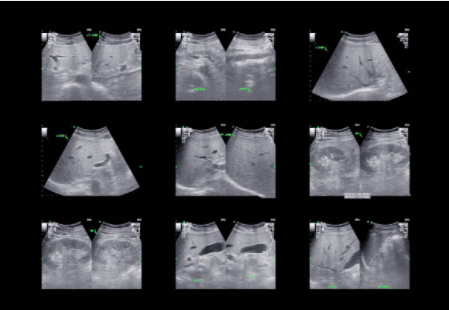

Несколько узловых образований печени на УЗИ

В этих случаях присутствуют выпуклости и изменения контура, а также аномалии текстуры. Может быть гепатомегалия. Несколько узлов могут также привести к появлению «снежной бури» или появлению «сита». Чаще всего различные типы поражений присутствуют в комбинации. Наблюдение нескольких метастазов требует идентичных плоскостей сканирования для каждого последующего обследования. Это требует точных анатомических ориентиров. Нумерация и измерение каждого отдельного узла являются обязательными этапами обследования.